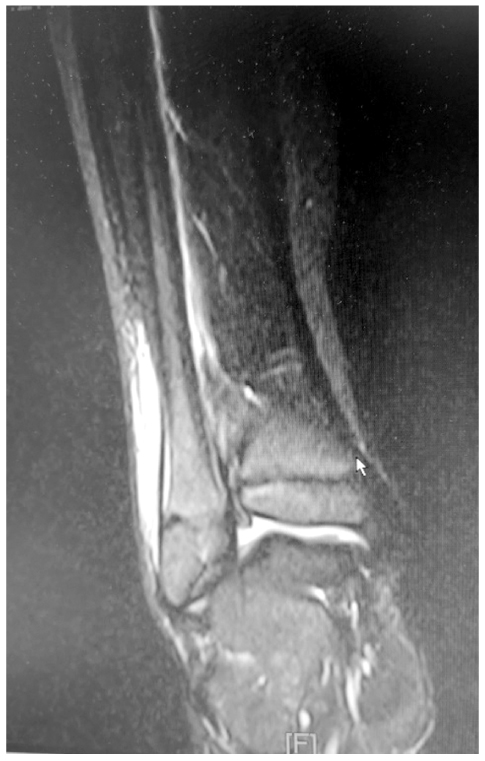

В 3 случае мальчику 10 лет на 5 сут болезни с болями и ограничением амплитуды движений в правом тазобедренном суставе после УЗИ (заподозрена псоас-гематома) выполнено МРТ, где кроме отёка ягодичных и подвздошной мышц справа, вероятно воспалительного характера, описан локальный отёк субхондральной поверхности правой подвздошной кости (рис. 4).

Рис. 4. Магнитно-резонансная томография правой подвздошной кости (мальчик 10 лет, 5 сут заболевания, фронтальная плоскость, Т2-взвешенное изображение): локальный отёк субхондральной поверхности правой подвздошной кости (стрелка).

Fig. 4. MRI of the acute hematogenic osteomyelitis of the right iliac bone (front plane, T2-weighted imaging) in a 10-y.o. child on day 5 of the disease. Local edema of subchondral surface of the right iliac bone (arrow).

Интраоперационно под надкостницей обнаружен гной (S. aureus в титре 105 КОЕ/мл), подтверждён диагноз «ОГО правой подвздошной кости; параоссальная флегмона».